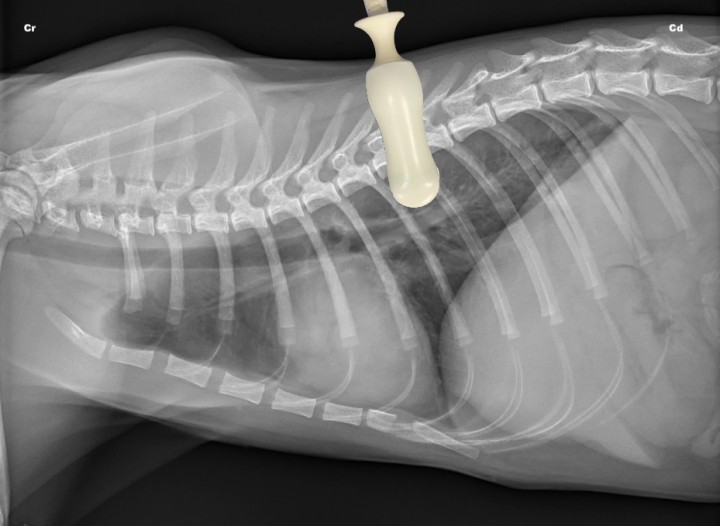

- Dorsocaudal (DC) bilateral: El transductor debe colocarse horizontalmente entre el 7º y 8º espacio intercostal de ambos hemitórax en su tercio dorsal (Fig. 1).[ Lisciandro G: Abdominal and thoracic focused assessment with sonography for trauma, triage, and monitoring in small animals. J Vet Emerg Crit Care 2011; 21(2): 104-122. [PubMed] ] Se examina de forma estática, colocando la sonda con el haz en plano longitudinal al paciente (transversal a las costillas) para maximizar el contacto del transductor con el borde pulmonar. Son los cuadrantes de elección para detectar neumotórax y patología pulmonar.[ Lisciandro G: Abdominal and thoracic focused assessment with sonography for trauma, triage, and monitoring in small animals. J Vet Emerg Crit Care 2011; 21(2): 104-122. [PubMed] , Boysen S, Lisciandro G: The Use of ultrasound for dogs and cats in the emergency room. AFAST and TFAST. Vet Clin Small Anim 2013; 43: 773-797. [PubMed] ]

<p>Radiografía lateral derecha de un gato sano en la que se observa la posición del transductor para valorar el cuadrante dorsocaudal (DC) de la T-FAST. Cr: craneal; Cd: caudal.</p>

Radiografía lateral derecha de un gato sano en la que se observa la posición del transductor para valorar el cuadrante dorsocaudal (DC) de la T-FAST. Cr: craneal; Cd: caudal.